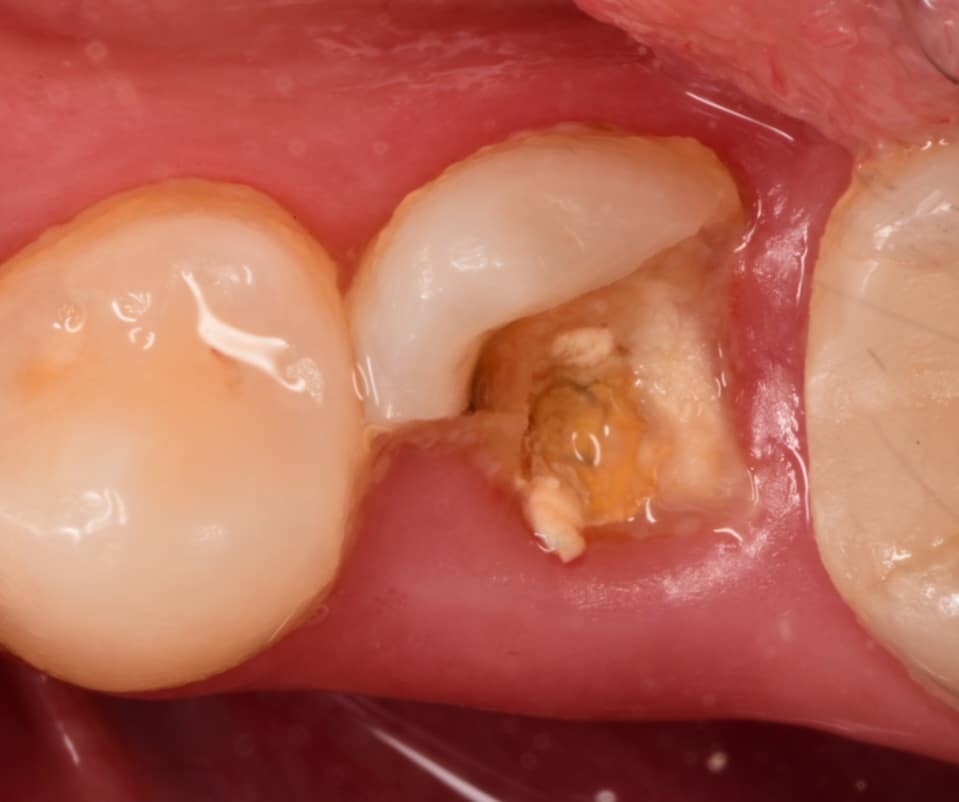

Isolation, look to the amount of tooth structure left under the gingival tissue, dentin quality looks good for bonding, so lets go with adhesive dentistry

Band adaptation, IDS with gold standard clearfil SE bond, RC with flowable composite,Ribbond placed inside the ever x flow, Ever x flow for dentin replacement,

Biobase ready